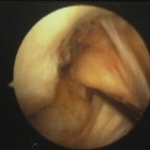

LCA roto puesto en evidencia al palparlo. Rodilla drcha. Vision artroscopica.